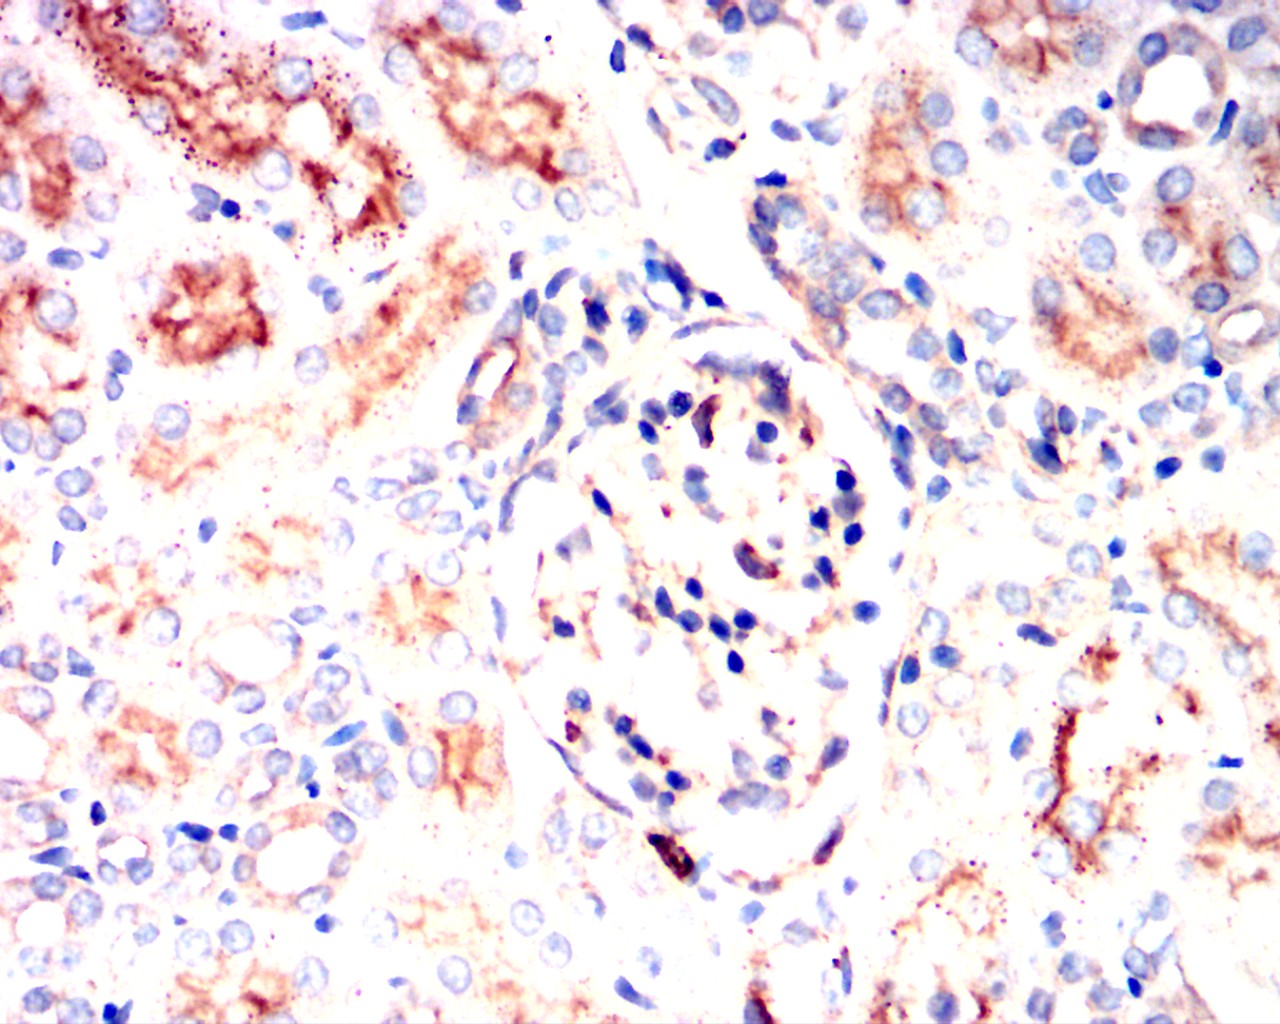

Immunohistochemical analysis of paraffin-embedded mouse kidney showing cytoplasmic localization using PIK3CA mouse mAb with DAB staining.